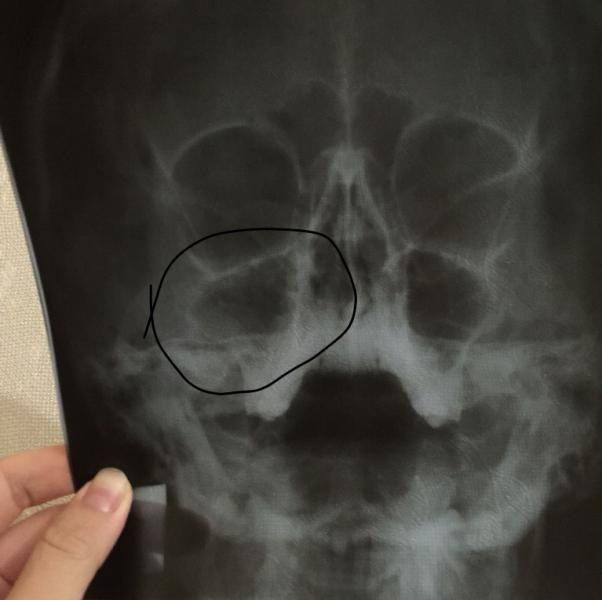

Говорят киста где отметила.У кого нибудь был такой диагноз?как лечили ?

Это она где у тебя?) не пойму, щека или ротовая полость? Дал маршал дойл💙